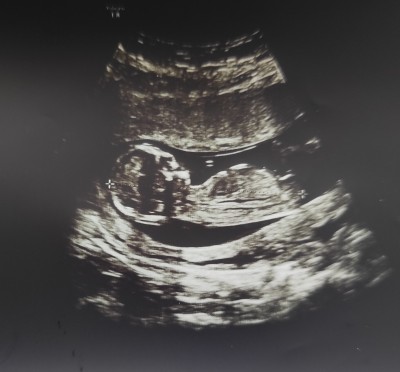

Bebegimin cinsiyetini sizce ne

Gebelik haftası 13